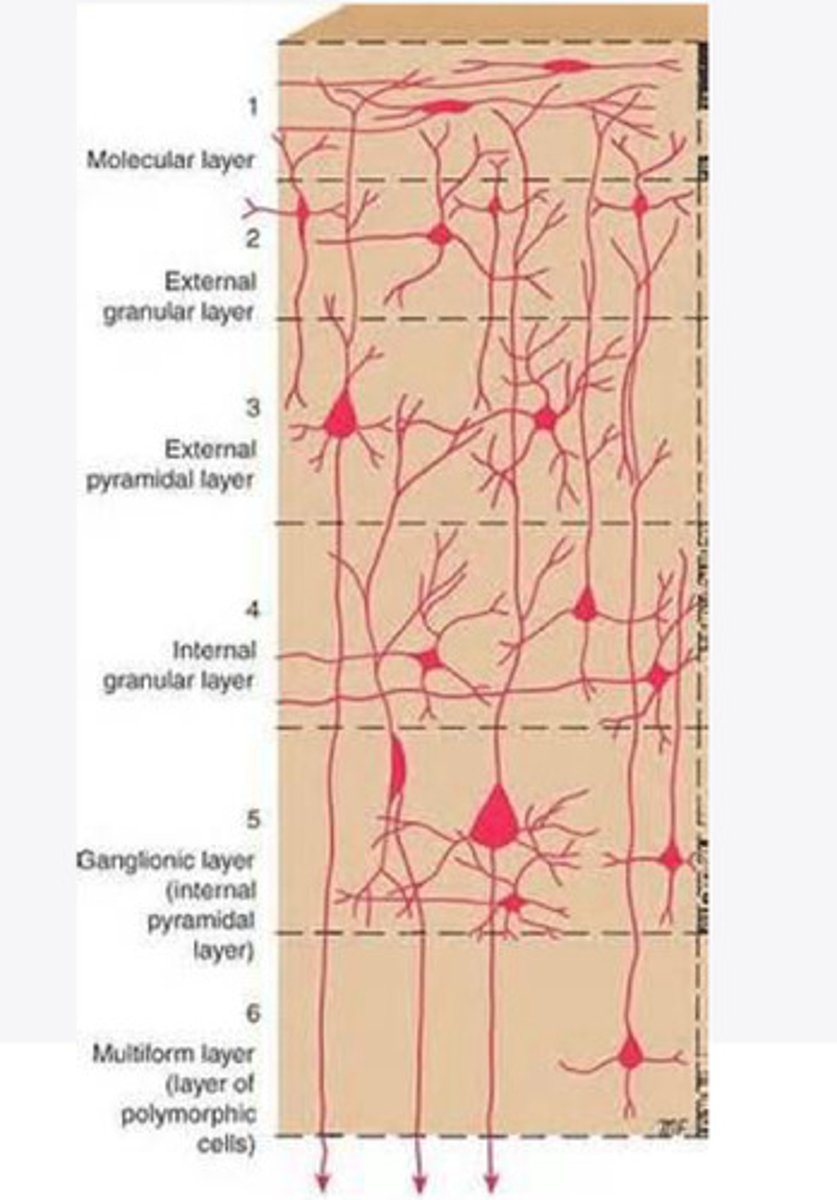

divided into 6 distinct layers, due to varying densities of cell body types within each layer

The cortex of the brain is divided into how many layers? Why is it divided into layers?

Layers of the cortex of the brain pic

2 and 4

What are the layers of the cortex that are associated with input?

3 and 5

What are the layers of the cortex that are associated with output?

molecular layer

What is the name of Layer 1 of the cortex of the brain?

very few cells

Does Layer 1 of the cortex have a lot or few cells?

receives dendrites from internal layers so it may actually function as a coordinating center where layers can communicate action

What does Layer 1 of the cortex do?

1

Every layer sends densities to Layer ____?

1

What layer serves as the "water cooler" of the brain?

external granular layer

What is the name for layer 2 of the cortex of the brain?

receives input from other cortical regions

What is the function of Layer 2 of the Cortex of the brain?

Stellate

What type of cells (stellate/pyramidal) would be most concentrated in Layer 2?

external pyramidal layer

What is the name for layer 3 of the cortex of the brain?

sends output to the other cortical layers

What is the function of Layer 3 of the cortex of the brain?

pyramidal

What type of cells (stellate/pyramidal) would be most concentrated in Layer 3 of the brain?

Layers 2 and 3

What layers are associated with association and commissural fibers?

Layer 3 - axons of cell bodies

Layer 2 - synapse into target areas in Layer 2

What part of the axons is in Layer 2/ in layer 3?

Layer 3 - external pyramidal layer

All axonal cel bodies for association and commissural fibers lie within what layer of the Cortex of the brain?

internal granular

** or called the striate cortex because it is so thick that you can see a line through this layer even in unstrained brain slides

What is the name for the 4th layer of the cortex of the brain?

receives input from the thalamus, geniculocortical layer, and other brainstem areas

What is the function for the 4th layer of the Cortex of the brain?

very thick within the vision, auditory, and somatosensory areas

Is Layer 4 thick or thin within SENSORY areas of the cortex?

Internal pyramidal

What is the name for Layer 5 of the cortex of the brain?

sends axons to the brainstem (corticobulbar) and spinal cord (corticospinal)

What is the function of Layer 5 of the cortex of the brain?

in motor areas of the cortex?

Where is layer 5 very thick in the brain?

the frontal lobe -- very motor heavy

What lobe of the brain will have a thick layer 5 of the cortex of the brain?

the multiform layer

What is the name of layer 6 of the cortex of the brain?

-sends axons back to the thalamus through corticogeniculate fibers

-modulates what information the thalamus sends to the cortex to control the strength of the signal received and modulate what you pay attention to

What is the function of layer 6 of the cortex of the brain?

no

Is layer 6 a motor layer?